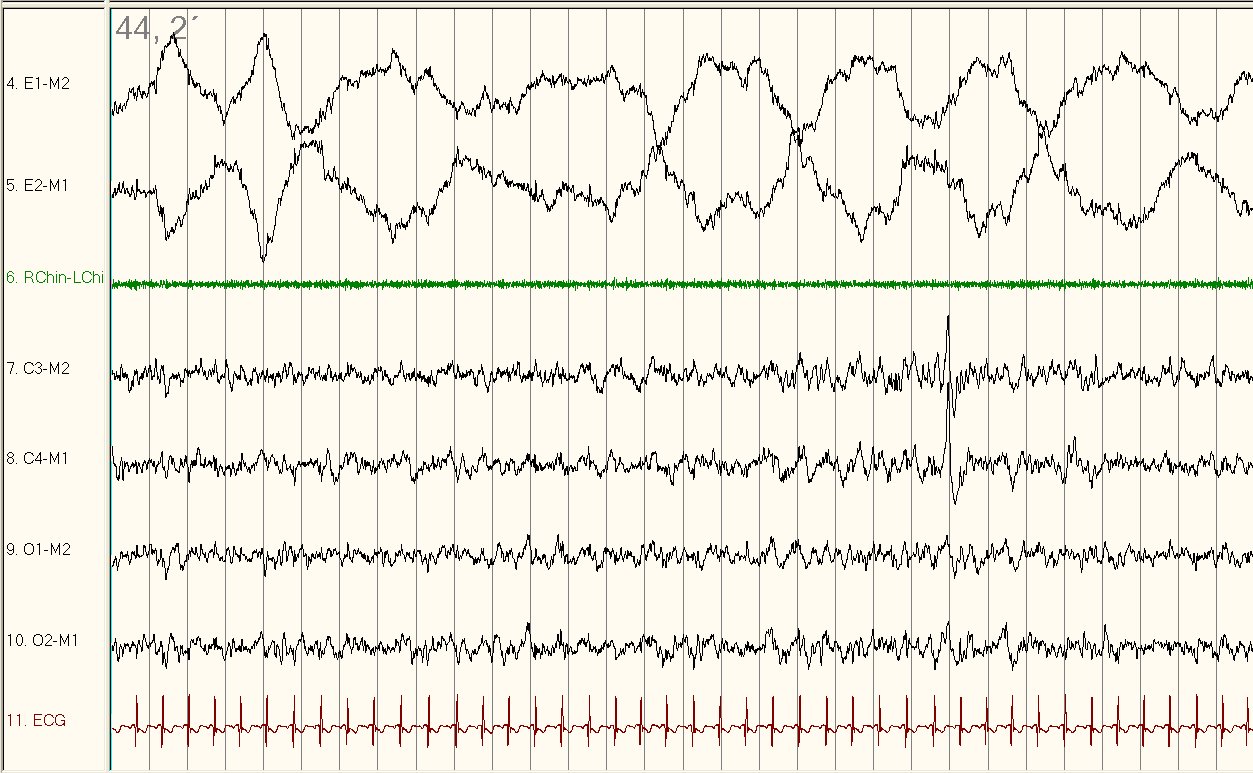

Figure 1

Figure 1 displays a 30-second tracing of stage N2 sleep with two rapid eye movements (red arrow) and a run of slow rolling eye movements (black arrows) on the electrooculographic (EOG) channel consistent with the use of Fluoxetine or another selective serotonin reuptake inhibitor (SSRI). Note that despite the rapid eye movements, the K complex (white arrow) seen on electroencephalogram (EEG) as well as the presence of muscle tone on chin electromyogram (EMG) indicates the eye movements are not part of stage REM sleep. As a comparison, Figure 2 provides a representative example of normal REM sleep in this patient with muscle atonia on chin EMG.